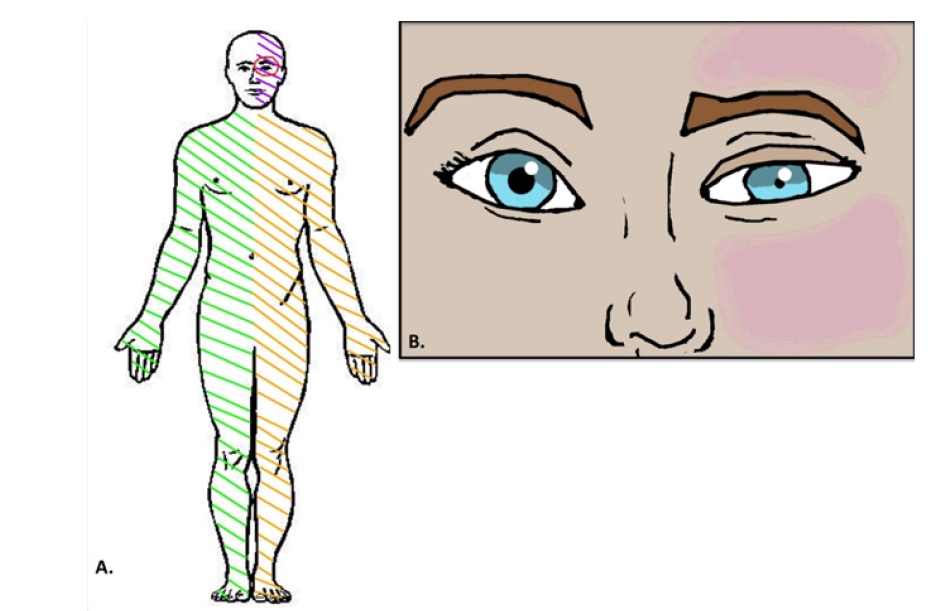

图8 延髓背外侧综合征的临床表现(五大症状):①交叉性感觉障碍(三叉神经脊束核+脊髓丘脑束)、②眩晕+眼球震颤(前庭核)、③共济失调(小脑下脚)、④吞咽困难/咽反射减弱/构音障碍(舌咽神经+迷走神经+疑核)、⑤Horner征(交感传导束)。(A)绿线表示对侧上下肢(脊髓丘脑束)的痛温觉减退;黄线代表同侧上下肢(小脑下脚)共济失调。左侧面部紫色线表示同侧面部(三叉神经脊束核核)痛温觉消失。红圈代表同侧眼(交感传导束)的Horner综合征。(B)Horner综合征。左侧(同侧)上睑下垂、面部少汗/无汗症和瞳孔缩小。